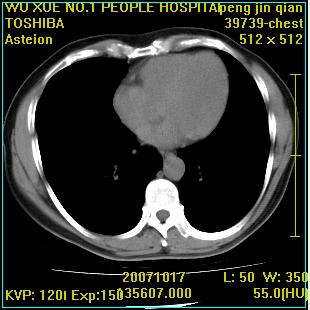

标题: CT10148:男,56岁,咳血。 [打印本页]

标题: CT10148:男,56岁,咳血。

左肺上叶尖后段较大团块影,边缘光滑,内见不规则裂隙样空洞,周围明显见细小结节及渗出,与肺门方向结构紊乱,另:左上叶尖段外侧 舌叶内侧 右上叶尖段及下叶背段均见片状致密影。考虑:继发性肺结核伴空洞形成!

左上肺后壁空洞,内壁不规则,可见壁结节;左上叶尖段外侧 舌叶内侧 右上叶尖段及下叶背段均见片状致密影。考虑:左肺肺癌并两肺继发性肺结核?

以下是引用卜一在2007-10-22 16:36:00的发言:[br]左肺上叶尖后段较大团块影,边缘光滑,内见不规则裂隙样空洞,周围明显见细小结节及渗出,与肺门方向结构紊乱,另:左上叶尖段外侧 舌叶内侧 右上叶尖段及下叶背段均见片状致密影。上腔静脉后淋巴结肿大,内有钙化。考虑:继发性肺结核伴空洞形成!

浸润型肺结核伴左上肺空洞形成,两肺播散灶